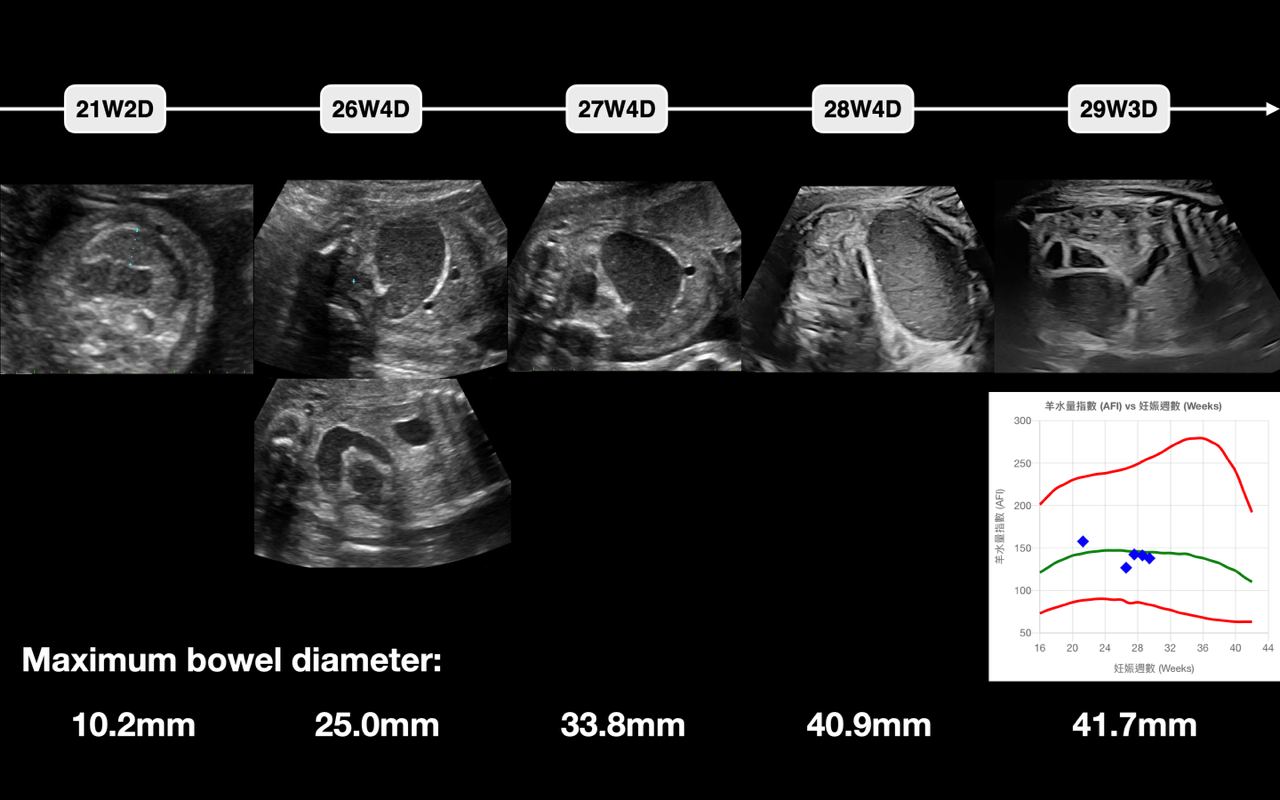

此個案是約莫21週在外院,因為胎兒腸子比較漲而轉介過來台兒診所尋求第二意見,超音波底下可見腸子較亮,沒有腹水,羊水量也正常,腸子最大徑為10mm,原肛(anal pit)可見,沒有發現其餘結構異常;後續做了TORCH screening結果為正常,也有請孕婦考慮進一步遺傳診斷。接著一路追蹤到29週(圖三),腸子越來越漲,但依舊是沒有腹水出現,羊水量也正常;針對漲大的腸子研究(圖四),認為是小腸接到大腸的部份發生腸道轉位異常(intestinal malrotation),懷疑之後腸子有可能會破裂,故安排會診小兒外科說明出生後可能的處置方式。

圖三、21週、26週、27週、28週、29週追蹤腸子的形態與最大徑。